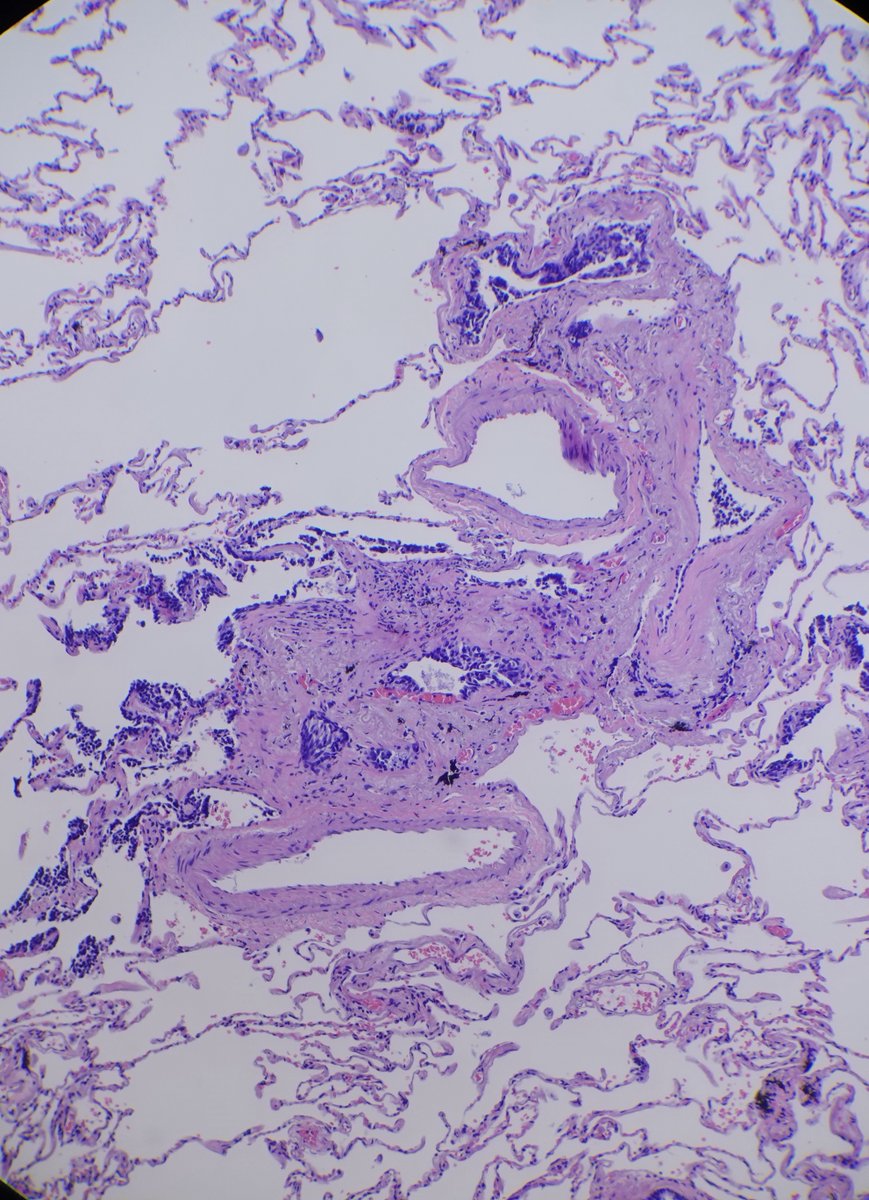

A: Lung Adenocarcinoma (in situ): Images showing emphysematous, lepidic growth pattern w/ increased presence of macrophages in the alveolar spaces, and a close-up of lepidic growing tumor cells around a blood vessel. @LungAssociation @UMRogelCancer #PulmonaryPath #DailyDX